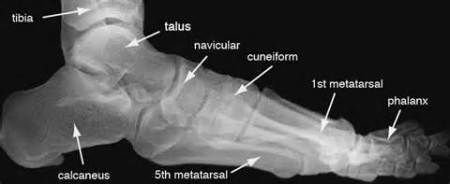

• Over 1,250 board review “styled” overt/covert Q-As [traditional rote memory and newer CBT, CPC and EBM cognitive format] with answers, short and long explanations and related high resolution infection graphics [x-rays, MRIs, CAT scans and color images]